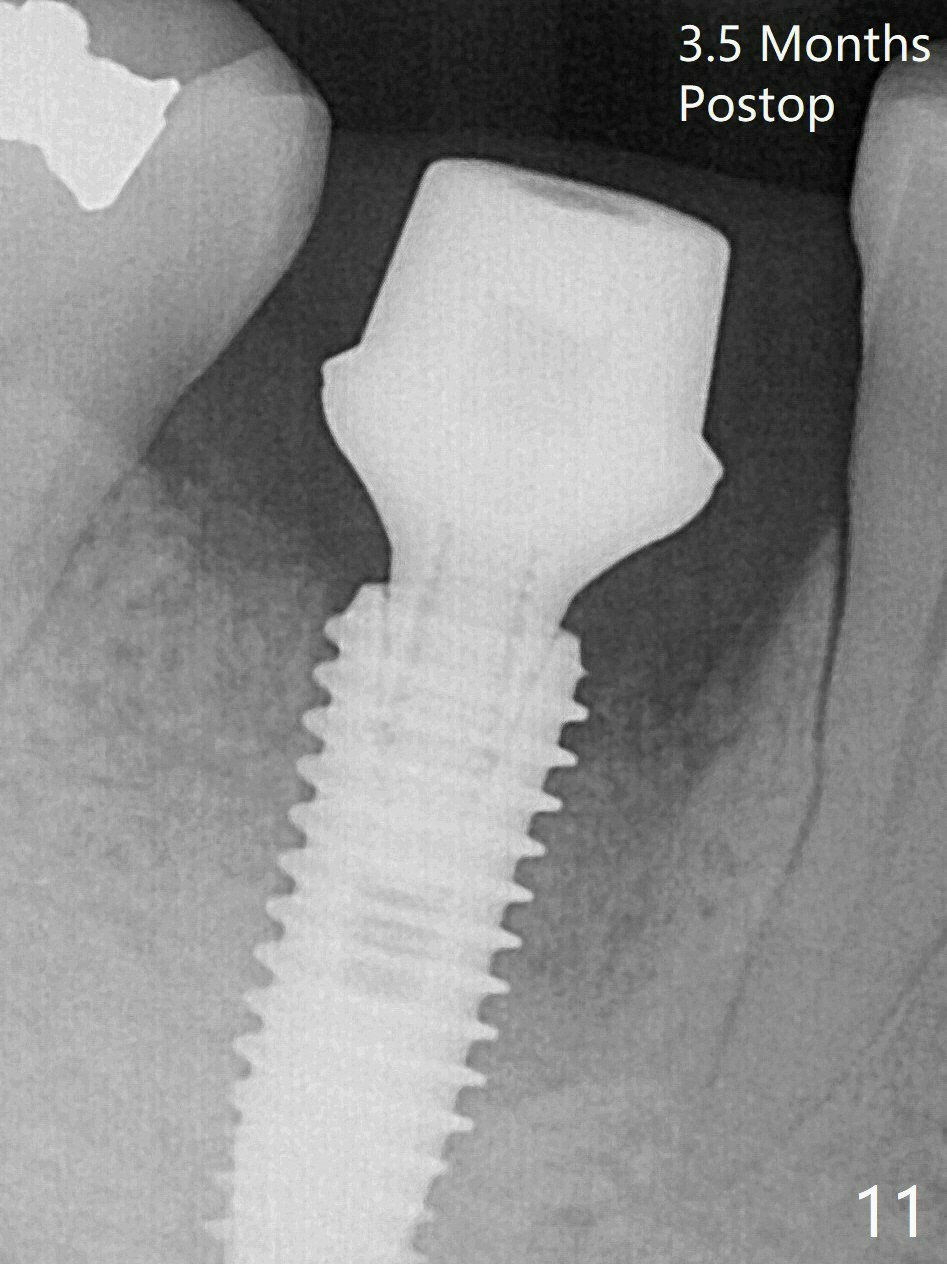

Preop oral Amoxicillin seems to be associated with reduction in the buccal and lingual (Fig.3 arrow) fistulae at #30, but there is mesiobuccal swelling (Fig.1 *) with 7 mm pocket (Fig.2). Osteotomy is initiated in the middle of the septum (Fig.3-5 S). As the osteotomy increases, it shifts mesially (Fig.6 arrow). Guided surgery is able to reduce shifting. A 5x13 mm implant is not seated completely (Fig.7) apparently due to osteotomy shifting. After removal of the bone from the osteotomy distally, the implant remains unseated with lower torque value (Fig.8). Following reuse of the 4.3 mm drill deeper by 1-2 mm, the implant is seated to a satisfactory depth (Fig.9 with increase in torque to 50 Ncm) with placement of Vera Graft (*) and a 7.5x4(3) mm abutment. After a second round of allograft placement (Fig.10 *), the implant is found to be 4 mm from the IAC. At the later stage of osteotomy, the coronal end of the septum is destroyed with loss of osteotomy depth landmark. It is apparent that the soft tissue landmark may be more reliable. The implant threads appear to be covered by the bone graft 3.5 months postop (Fig.11). The abutment is changed to 6.5x5(3) mm one before impression with minor margin prep. The bone density seems to increase 5 months postop, i.e., immediately post cementation (Fig.12) and 10 months postop (5 months post cementation (after retightening abutment), Fig.13 (*)). Periimplantitis develops mesiobuccally, consistent with bone loss 1 year 7 months post cementation (Fig.14 *); the implant seems to have been buccally placed. Bone graft is necessary with PRF or GEM21S if the vein is small and 6-month membrane with a hole around a 7.5x4(4) cemented abutment for easy wound closure. Take 5x5 CM CBCT to determine which wall has defect, buccal or lingual. Check mesial contact. If so, remove the crown, reseat the abutment (possible incomplete seating) and re-impress after bone graft.